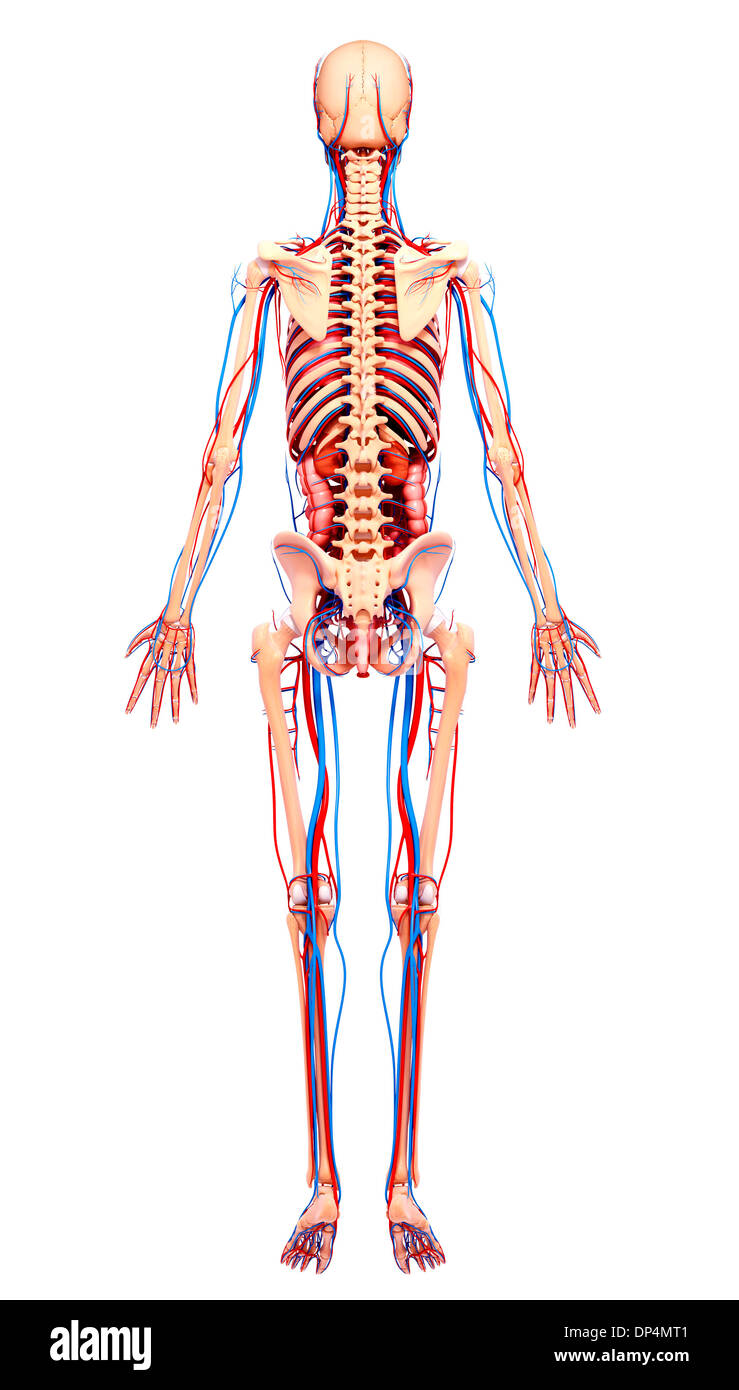

, Artwork Banque D'Imageshttps://www.alamyimages.fr/image-license-details/?v=1https://www.alamyimages.fr/artwork-image65257697.html

, Artwork Banque D'Imageshttps://www.alamyimages.fr/image-license-details/?v=1https://www.alamyimages.fr/artwork-image65257697.htmlRFDP4MT1–, Artwork